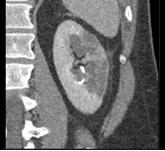

男,47岁,左侧腰痛、叩击痛,请结合图像,选择最可能诊断 ( )A、左肾脓肿B、左肾挫伤C、左肾癌D、左肾梗死E、左侧肾盂肾炎

问题 男,47岁,左侧腰痛、叩击痛,请结合图像,选择最可能诊断 ( )

选项 A、左肾脓肿 B、左肾挫伤 C、左肾癌 D、左肾梗死 E、左侧肾盂肾炎

答案 D